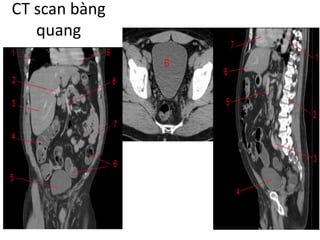

CT	HỆ	NIỆU

— Vai trò chính và quan trọng trong khảo sát hệ niệu

— Chỉ định: rộng rãi

Chấn thương, viêm, u, bất thường bẩm sinh đường

niệu.

Bất thường mạch máu…

CT	thận

• Protocol

- Thì không thuốc

- Thì động mạch

- Thì vỏ tủy

- Thì thận đồ

- Thì bài tiết

Thì không thuốc

• Khảo sát:

- Sỏi,	vôi hóa

- Xuất huyết,	tụ máu

- Mỡ đại thể trong u	thận

dạng đặc

- Tính mức độ bắt thuốc

trong các loại u

Sỏi thận+	vôi hóa động mạch

chủ bụng

Thì động mạch

• 15-25	giây sau

tiêm thuốc tương

phản.

- Hẹp động mạch

thận

- Stent	động mạch

- Chảy máu cấp

- Bản đồ mạch máu

thận Chảy máu hoạt động/	bn

chấn thương

Thì vỏ tủy

• 25- 70	giây sau tiêm

thuốc tương phản.

- Hình thái thận

- Khối ở	thận giàu mạch

máu

- Mạch máu thận(	phình,

dị dạng,	dò)

- Tìm di	căn

Thì thận đồ

• 80-180	giây sau tiêm thuốc tương phản

- Tổn thương trong thận

- Tĩnh mạch thận,	tĩnh mạch chủ dưới

Thì bài tiết

• >	180	giây sau tiêm

thuốc tương phản

- Hệ thống bài xuất

- Khối ở	thận:	đánh giá

xâm lấn xoang,	wash

out

- Tổn thương bắt thuốc

muộn

Chấn thương thận có

tổn thương đường bài

xuất

CT	scan	Niệu quản

Giải phẫu:

- Dài 25-30 cm và có ba

phần:

Niệu quản bụng: từ thận

đến khung xương chậu

Niệu quản Chậu: từ

khung xương chậu đến

bàng quang

Niệu quản nội màng hoặc

nội mạc: trong thành bàng

quang

- Đường kính bình thường

</=3mm [1]

CT	scan	bàng quang

FEMALE

MALE

CT	scan	bàng

• Chỉ định:

Các bệnh lí tại bàng quang:	viêm,	u,	túi thừa,

sỏi.

Bệnh lí vùng chậu xâm lấn bang	quang:	K	cổ tử

cung,	K	trực tràng,	K	tiền liệt tuyến…